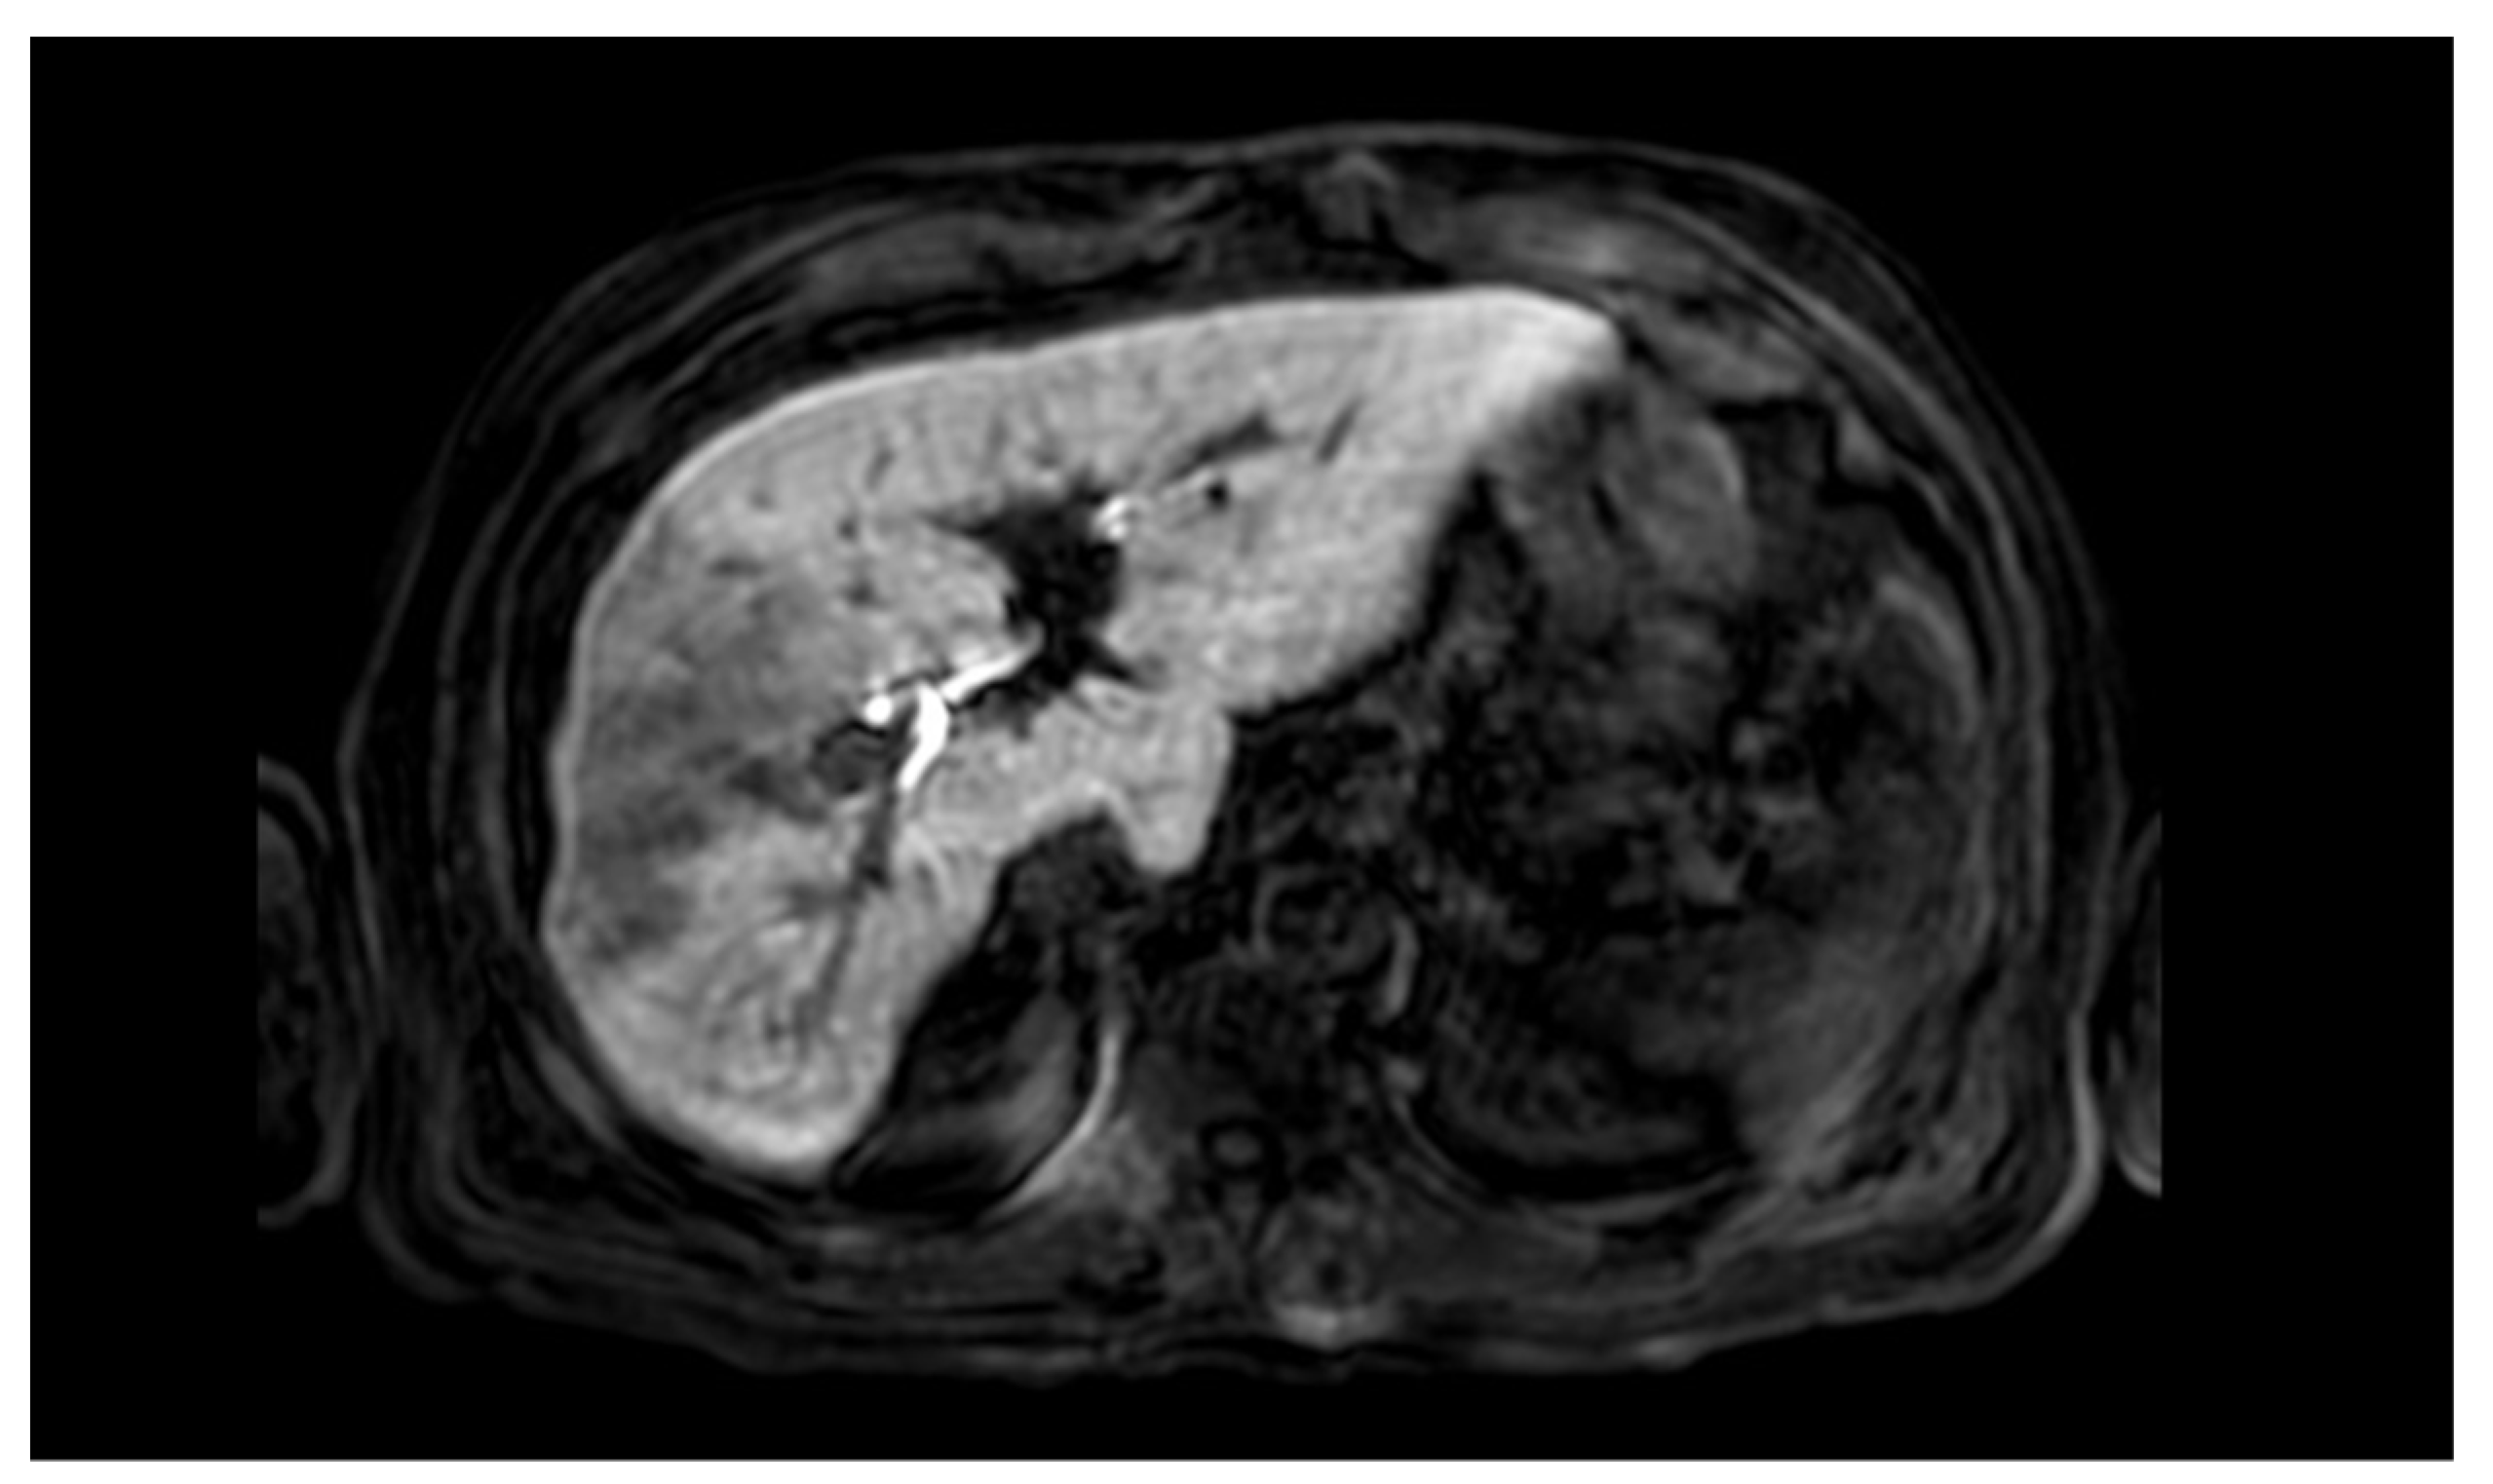

3.1. Case Presentation